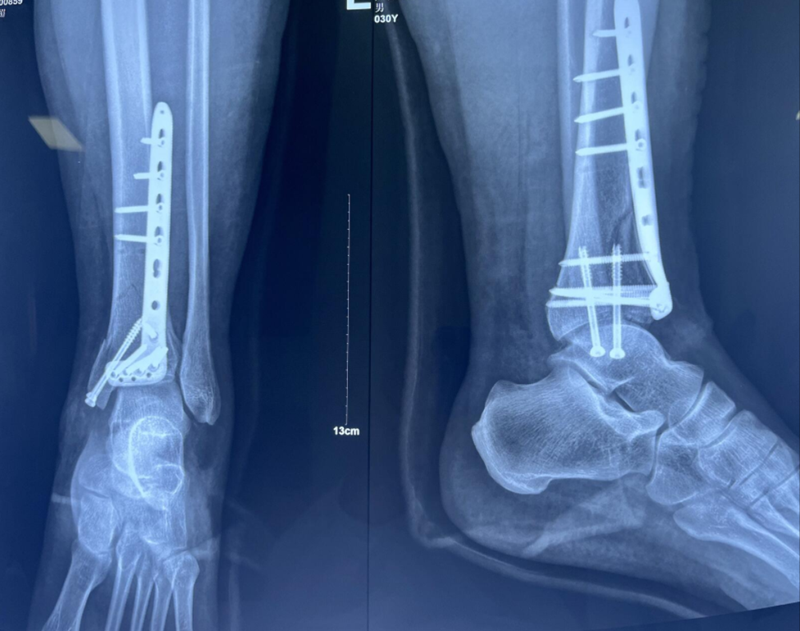

x男,30岁,体重100kg,在五楼擦玻璃时坠落到四楼致伤2天。

诊断:左胫骨平台后柱骨折,后交叉韧带撕脱骨折,左踝关节pilon骨折3型。

图8 Pilon骨折3型

术后影像学资料: